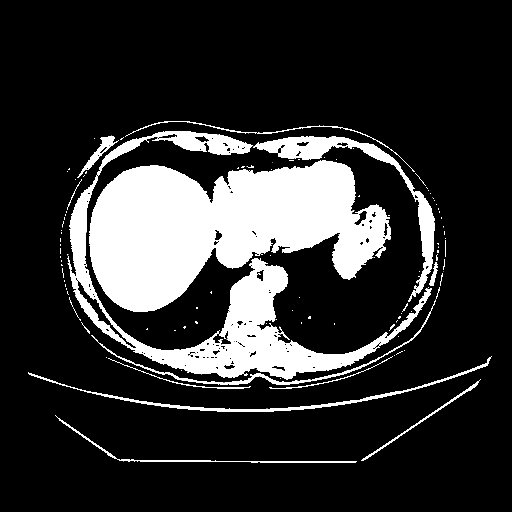

Reconstructed NATIVE CT scan (cycle consistency)

Full window (WL 1023.5, WW 4095 β†’ Low βˆ’1024, High +3071)

Actual HU range: [-1024.0, 3071.0]